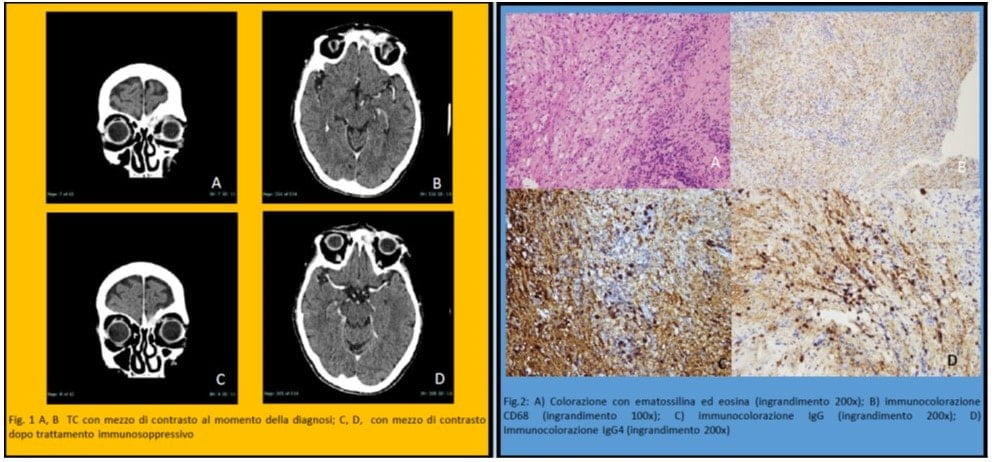

molli della palpebra sinistra che erode la parete mediale dell’orbita sinistra e il processo nasale dell’osso frontale. (Fig.1) In anestesia locale è stata eseguita una biopsia incisionale della massa. Il primo esame istopatologico non è stato conclusivo: processo infiammatorio con presenza di istiociti, linfociti, granulociti e plasmacellule, con necrosi della struttura muscolare. Sono stati richiesti livelli sierici di immunoglobuline, inclusa IgG4, ed è stata eseguita una seconda biopsia in anestesia generale. Il livello sierico di IgG4 era 654 mg / dL e l’esame patologico ha evidenziato la presenza di un infiltrato

linfocitico intenso e intenso principalmente plasmacellulare, con istiociti e granulociti. L’immunoistochimica ha evidenziato la presenza di plasmacellule con un rapporto di cellule positive IgG4 / IgG> 50%.

Questi risultati hanno consentito una diagnosi definitiva della malattia oftalmica correlata alle IgG4 come proposto da Umehara et al.:

A. Gli studi di imaging mostrano un ingrossamento della ghiandola lacrimale, del nervo trigemino o del muscolo extraoculare, nonché masse, ingrossamento o lesioni ipertrofiche in vari tessuti oftalmici.

B. L’esame istopatologico mostra una marcata infiltrazione di linfociti e plasmociti e talvolta fibrosi. Si osserva spesso un centro germinale. I plasmaciti IgG4 þ sono trovati e soddisfano i seguenti criteri: rapporto tra cellule IgG4 þ e cellule IgG þ del 40% o superiore, o più di 50 cellule IgG4 þ per campo ad alta potenza

C. L’analisi del sangue mostra IgG4 sieriche elevate (> 135 mg / dl)